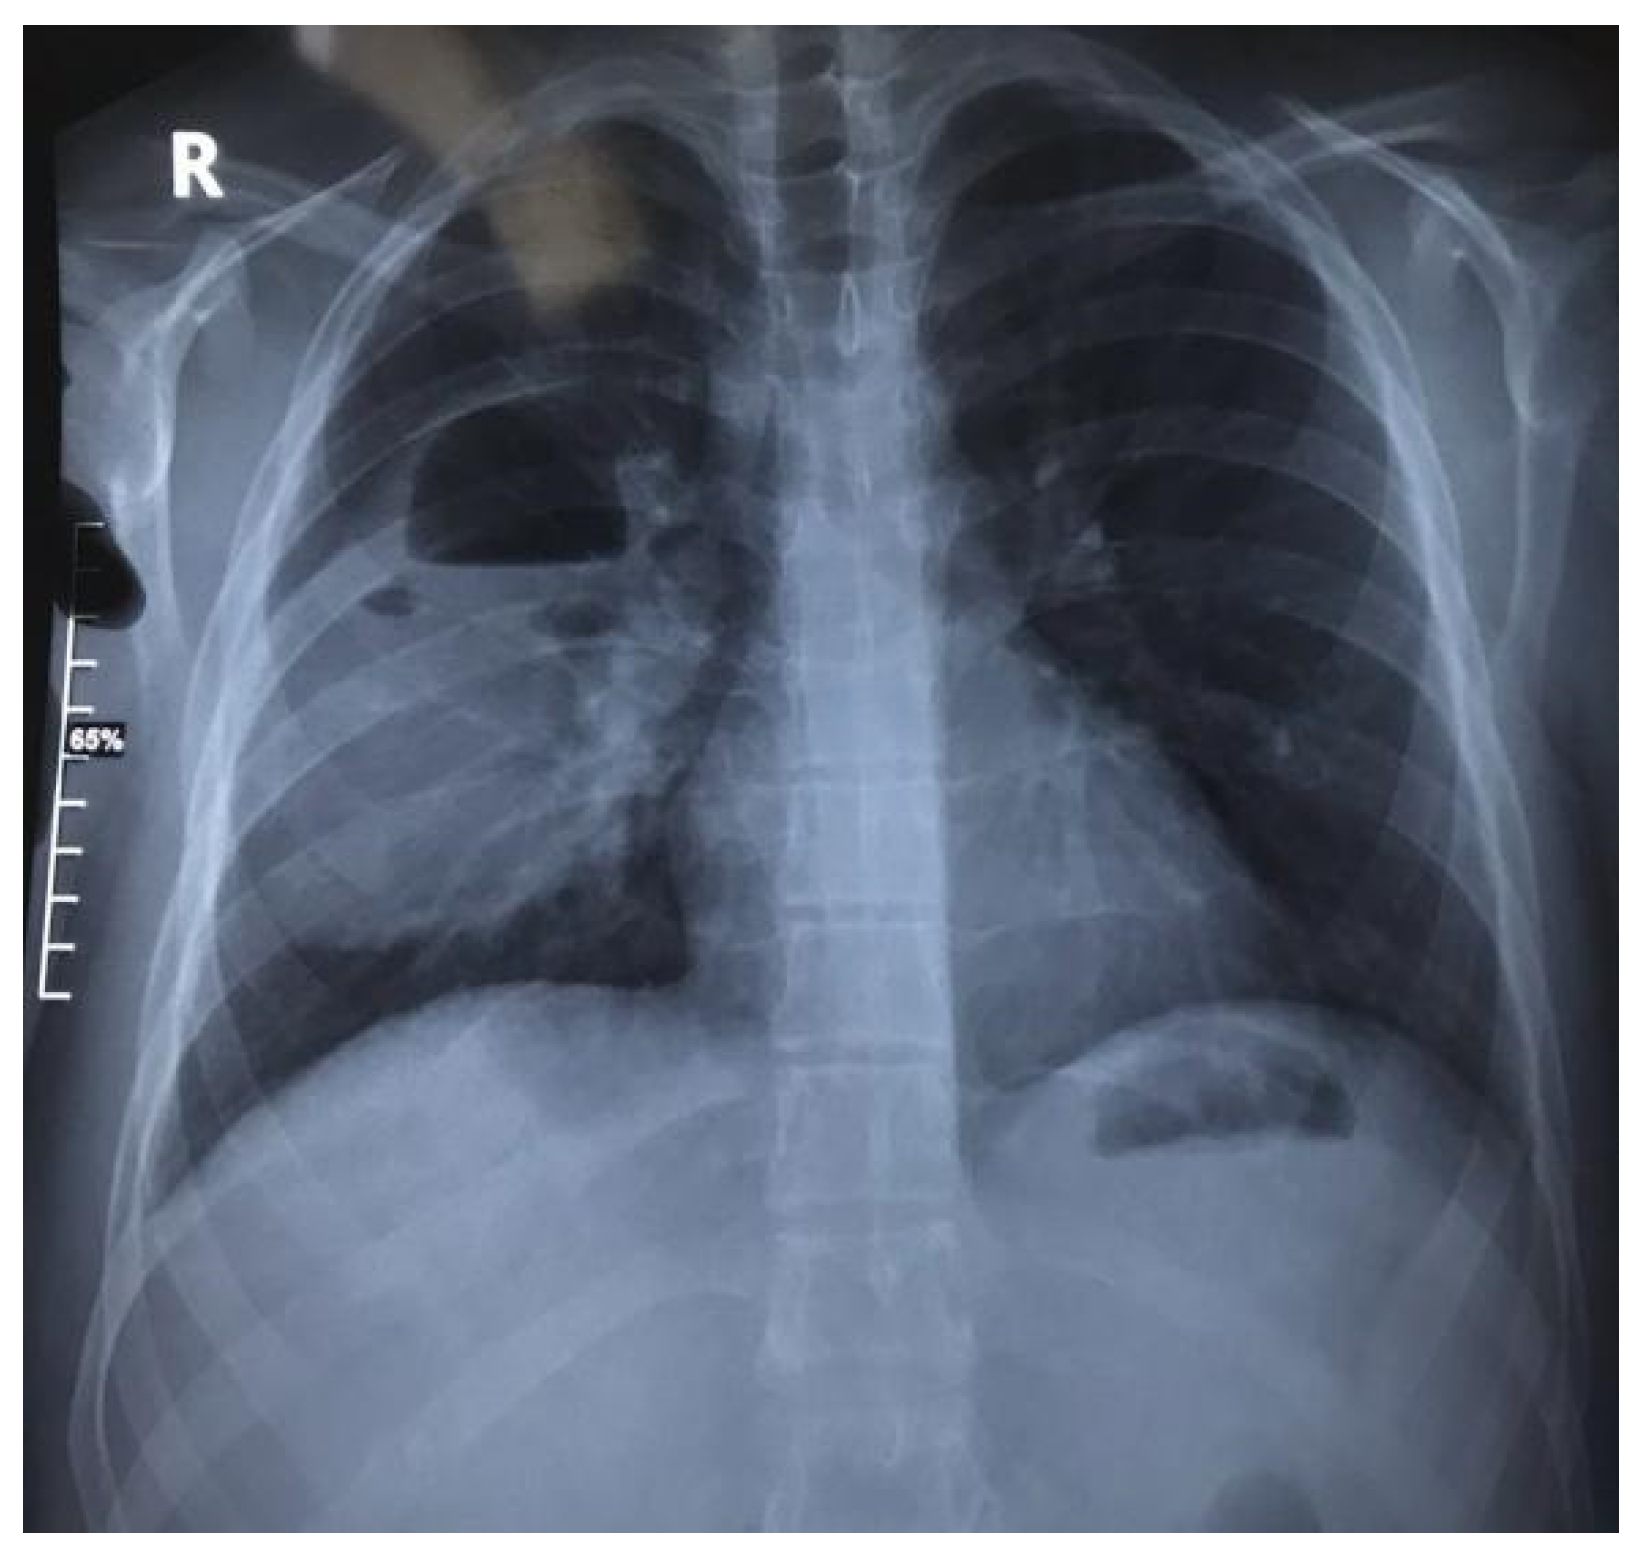

1.9.1. Case 1